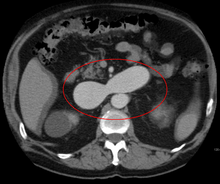

- Computerized tomography (CT) scan is a noninvasive X-ray to view the anatomical structures within the brain to detect blood in or around the brain. A newer technology called CT angiography involves the injection of contrast into the blood stream to view the arteries of the brain. This type of test provides the best pictures of blood vessels through angiography and soft tissues through CT.

AVMs can occur in various parts of the body: